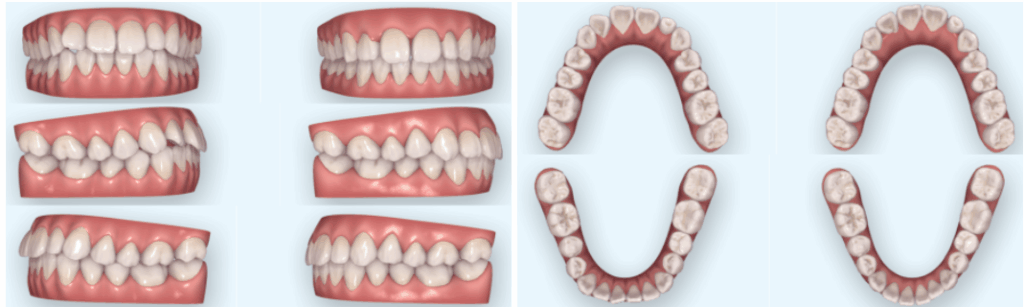

구강 내 모습을 확인해 보니

위 아랫니가 삐뚤빼뚤한 것을

확인할 수 있었는데요.

삐뚠 치열로 인해

왼쪽 위 측절치는

조금 틀어져 있었습니다.

더불어, 왼쪽 위 측절치가

오른쪽 자연치에 비해

작은 것을 관찰할 수 있었는데요.

| 5. 치료 후 변화

25.01.07

먼저, 작아 보이던 앞니가

자연스럽고 균형 있는 치열 속에 녹아들었고,

삐뚤거렸던 배열도 해소되었습니다.